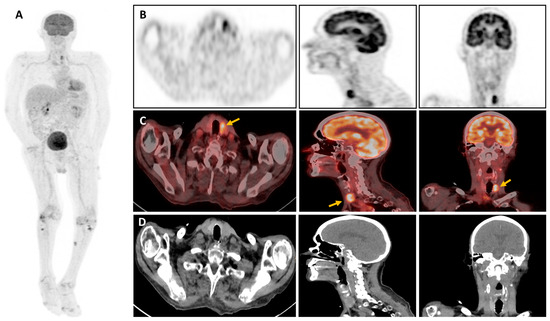

Figure 2. In this challenging context, nuclear medicine imaging has gained in popularity, particularly through the performance of 2-[18F]-fluoro-2-deoxy-D-glucose positron emission tomography combined with computed tomography (18F-FDG-PET/CT) in the diagnosis and monitoring of infectious diseases [8]. 18F-labeled FDG is a glucose analog absorbed by cells via a membrane transporter (GLUT-1 and GLUT-3) and sequestered after phosphorylation. Therefore, its intracellular concentration is proportional to the cell’s metabolism [8]. Typically, cellular use of glucose rises in leukocytes activated by infection and inflammation, leading to intense uptake of 18F-FDG, detectable by PET/CT [9]. 18F-FDG-PET/CT of the patient: (A) Maximum Intensity Projection (MIP) of the entire body. (B) Maximum 32 Intensity Projection (MIP) of the head section passes at the level of the thyroid compartment. (C) fused PET/CT images, 33 (D) CT-images showing the hypermetabolic thyroid nodule (yellow arrow). Due to the heterogeneous presentation of IA, 18F-FDG-PET/CT is a consistent tool, particularly in the early stages of the disease, and for the detection of extrapulmonary lesions [10]. According to the literature, the metabolic activity of aspergill nodules is not necessarily high and may vary (low to high uptake) depending on aggressiveness and form (acute or chronic IA) [11]. Some authors have reported different metabolic imaging presentations of aspergillosis lesions; a cold nodule with discrete surrounding metabolism, an iso-metabolic one when glucose uptake is similar to or less than the mediastinal blood pool, and a hypermetabolic one when glucose uptake is greater than the mediastinal blood pool as in our patient (Figure 2A,B) [11,12]. Hence, IA can result in a wide range of clinical manifestations of aspergillosis and a broad spectrum of possible presentations on 18F-FDG-PET/CT imaging. In our view, the thyroid gland is an unusual localization as it is extremely resistant to infection owing to its high iodine level, hydrogen peroxide production, extensive lymphatic and vascular supply, and encapsulated location [12]. Aspergillosis predominantly affects the lungs, invading the lung parenchyma and vasculature, but may also spread by a hematogenous route to various organs such as the central nervous system, heart, kidney, skin, soft tissues, and liver [5]. Once the thyroid gland is invaded, it may show variability in thyroid bioassays, ranging from hyperthyroidism due to hormone release from follicular cell lesions to hypothyroidism or euthyroidism, as in our patient [10]. According to the literature, innate and adaptive immunity have long been recognized as playing a crucial role in combating aspergillosis infection [13,14,15]. The innate immunity mediated by macrophages, neutrophils, natural killers, and plasmacytoid dendritic cells is essential for phagocytosis and fungal damage. Therefore, in our patient, it appears highly likely that the iatrogenic immunosuppression induced by the drugs used in the liver transplant significantly disrupted the patient’s immune homeostasis and led to the development of this opportunist infection, which spread from his lungs through his bloodstream to his thyroid gland. Moreover, Aspergillus fumigatus has a greater proclivity than other Aspergillus species to invade the thyroid gland and potentially induce significant destruction of thyroid tissue [16].